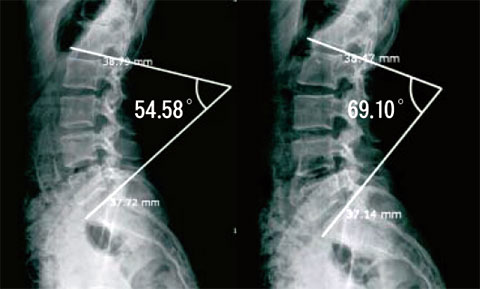

김혜원 씨는 맨발 상태로 척추 X선을 찍었을 때 첫 번째 요추(허리뼈) 아랫면과 첫 번째 천추(엉덩이뼈) 윗면이 이루는 각도가 54.58도였다. 3㎝ 높이 구두를 신었을 때 이 각도는 63.06도, 7㎝ 높이 구두를 신었을 때는 65.27도, 11㎝ 높이 구두를 신었을 때는 69.10도까지 커졌다. 맨발일 때와 하이힐을 신었을 때 척추 뼈가 휘어진 각도는 14.52도나 차이가 났다. 김서경 씨 역시 맨발 상태에서 X선을 찍었을 때에는 57.69도였던 허리 각도가 11㎝ 높이의 하이힐을 신었을 때에는 63.63도로 확 커졌다. 박 교수는 "요추와 천추가 이루는 각도는 50~60도가 정상이다. 이 각도가 60도 이상이면 척추 뼈가 병적으로 휘어진 요추 전만증으로 진단한다. 물론 하이힐을 신은 상태에서 60도 이상 휘어졌기 때문에 요추 전만증으로 진단할 수는 없으나, 허리에 심하게 부담이 가해진 상태인 것은 틀림없다"고 말했다.

맨발로 섰을 때(왼쪽)와 11cm높이의 하이힐을 신었을 때(오른쪽) 척추 엑스선 결과. 첫 번째 허리뼈 아랫면과 첫 번째 엉덩이뼈 윗면이 이루는 각도를 비교했다. 하이힐을 신으면 허리가 휘어지므로 이 각도가 커진다.